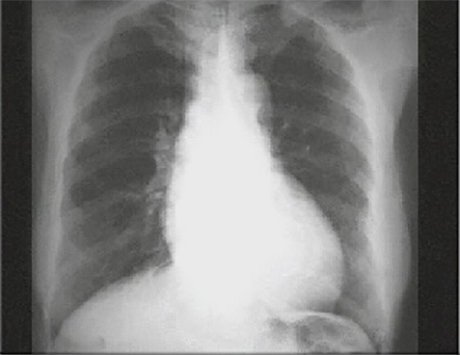

These chest X ray shows left ventricular enlargement and aortic dilation.

Left ventricular enlargement, or dilation, is suggested by the increased

cardiothoracic ratio, with the

apex of the cardiac silhouette displaced downward into the left.

Aortic dilation is demonstrated by the

widened superior mediastinal shadow bilaterally.

This chest X ray is consistent with chronic aortic regurgitation.